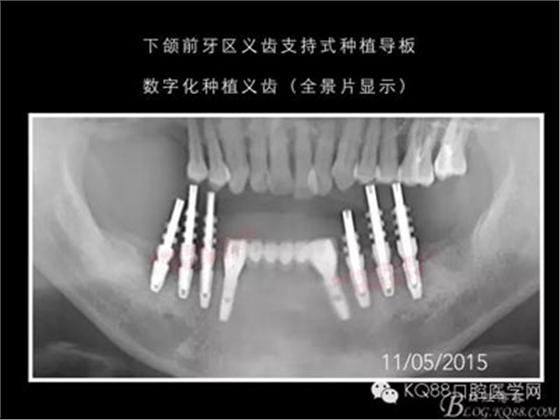

下面的種植病例是為患者提供全口牙齒治療修復完整過程的下頜部分,我們門診和患者共同配合下目前取得了較好的修復效果,即將開始的上頜牙齒治療修復過程仍然艱辛。